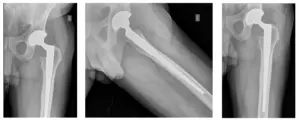

Patient had followed-up to review X-rays. Patient is doing well and will follow-up in one year to monitor his left THA. Patient is doing well and has no pain.

X-Rays of Left THA. X-rays reveal no fractures and good alignment of Left THA